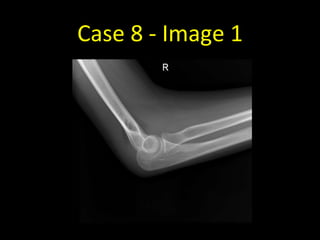

Case 8 - Image 1

Case 8

• Not all fractures are visible on

radiographs, particularly in the

acute setting

• There may however be signs of

the fracture in the surrounding

soft tissues

• Remember, fat allows the

transmission of a relatively large

number of x-ray photons and

therefore appears dark

• Note the two triangles of fat anterior

and posterior to the distal humerus

• These are the fat pads that have been

displaced by fluid in the elbow joint

• In practice, this is presumed to be due

to a radial head fracture although the

fracture line is not visible